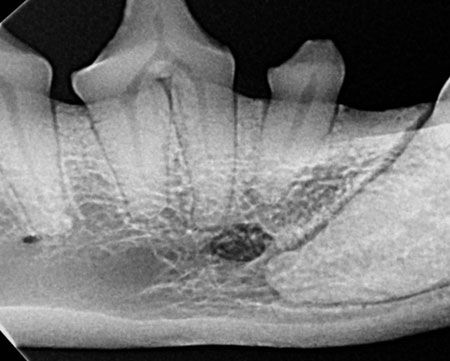

Dental X-ray Interpretation

✔  Understand the importance of dental radiographs and how to interpret them correctly ✔  Learn how to identify normal radiographic structures in animals ✔  Avoid misdiagnosing oral pathology by distinguishing artifacts from true abnormalities ✔  Guidance to navigate radiographic structures to determine if the view is normal or if there is anything of concern ✔  Cover what treatment options are appropriate and why